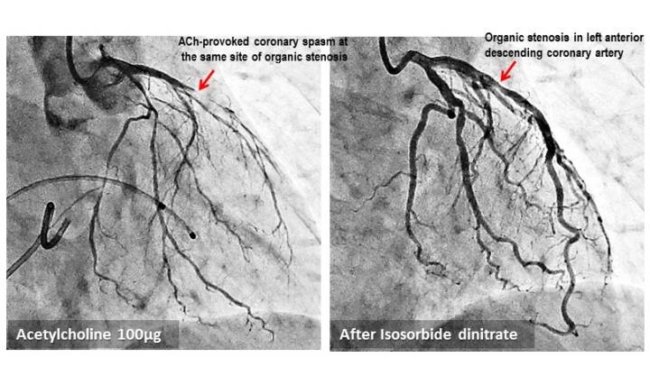

Blood Vessel Spasms Linked To Heart Attacks

Spasms at sites of coronary artery narrowing could be used a predictor for heart attacks, paving the way for early detection.